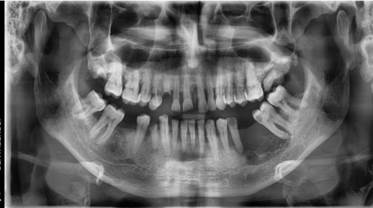

Figura 4.

Ortopantomografia: Se evidencia imagen radiolucida en cuadrante III, con un diámetro aproximado de 3cm, bordes definidos y extensión limitada a espacio ausente entre OD 35 y OD 36.